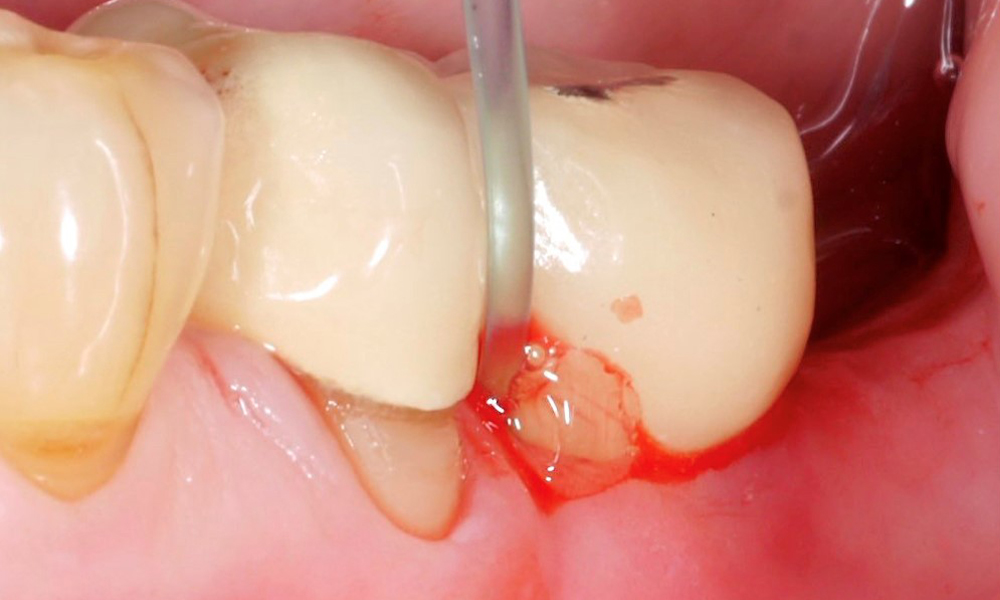

İmplant yüzeyinin etkin ve başarılı bir şekilde temizlenmesi, peri-implantitis vakalarının tedavisinde kesinlikle en önemli faktörlerden biridir. Daha önceki bir raporda (Cerrahi olmayan peri-implantitis tedavisi ve altın standart ),.2022 sonbaharında düzenlenen ve peri-implantitis vakalarının tedavisi için mekanik temizlik konusunu işleyen 18. Avrupa Periodontoloji Çalıştayı'nın sonuçları tartışıldı. İmplant yüzeyinin mekanik temizliğini ek kimyasal temizlikle destekleme seçeneği olduğu açıklandı.

İmplant yüzeyinin ek kimyasal temizliğine ilişkin mevcut kanıtlar, Waal ve arkadaşları tarafından 2022 yılında özetlenmiştir. Ancak, ne yazık ki mekanik temizlemeye benzer şekilde burada, peri-implant koşulları için net tedavi kılavuzları bulmak için hala çok az sayıda iyi yürütülmüş çalışma olduğu sonucuna varılmıştır.. Bu nedenle bu araştırma grubu, sistematik incelemede 'kimyasal temizlik' konusunda yalnızca üç çalışmayı tanımlayıp özetleyebildi.

İki çalışma, anti mikrobiyal fotodinamik terapinin etkisini inceledi. Diğer çalışma, özellikle implant yüzeyini temizlemek için jelin etkisini inceledi.

Her üç çalışmada da bu kimyasal yöntemler, örneğin ultrasonik veya havayla cilalama işleminden oluşan submukozal, mekanik temizlik için de kullanılmıştır. Sondalamada kanama veya tedavi başarısı gibi diğer tüm parametreler yetersizken, her üç çalışma da sondalama cep derinliklerinin azalmasıyla ilgili olarak daha iyi sonuçlar gösterdi.

Kısacası, özellikle implant yüzeyini temizlemek için kimyasal katkı maddeleri mantıklı olabilir, ancak gerçekten spesifik bir yöntem önerebilmek için yeterli sayıda hasta ve yeterince uzun takip süresi ile iyi yürütülmüş çalışmalara gereksinim vardır. Bu nedenle, mekanik temizleme raporunda daha önce özetlendiği gibi, aşağıdakiler hala geçerlidir: